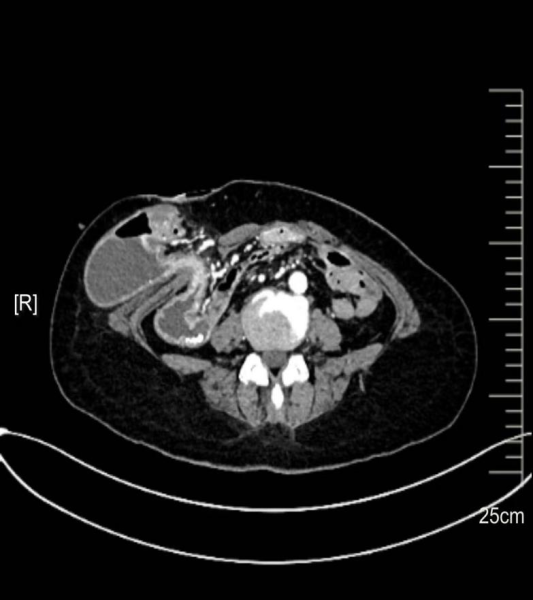

随后,李国东主任团队对张女士的病情进行了全面分析,并准确给出了:回肠造口旁疝、造口不全梗阻、继发性重度贫血、重度营养不良的诊断。但是张女士和普通的“造口旁疝”手术之间耸立着另一座“大山”——张女士十年前接受过的全结肠切除手术等三次手术必然导致其腹腔内存在广泛且严重的粘连,这会大大增加此次手术的难度和风险。一方面,粘连组织的界限十分模糊,手术中非常容易出现仅剩的小肠损伤、触碰血管导致大出血等问题;另一方面,患者本身存在贫血和营养不良的情况,术后恢复能力较差,手术耐受性也远低于普通患者,这无疑给手术和术后护理都带来了巨大的挑战。为确保手术的顺利进行,李国东教授团队联合麻醉科、手术室、临床营养科组成多学科诊疗协作组,围绕患者的病情、手术方案制定、术中可能出现的风险及应对措施、术后护理重点等问题展开了深入的分析和探讨,并最终形成“张女士专属个体化治疗方案”。经过认真的术前准备和系统的营养支持治疗、张女士的营养指标和贫血症状得到了明显的改善,机体各项指标也最终达到了手术标准。

正如术前预判的那样,患者腹腔内的粘连情况比想象中更为严重,肠管、网膜、腹壁等组织紧密粘连在一起,几乎看不到正常的解剖结构。李国东主任凭借丰富的手术经验、精细的手术操作以及稳定的心理素质,经历了近4小时的高强度、高难度手术,最终成功完成了“病变造口切除、造口旁疝修补、新造口重建和腹壁修补”的全部手术步骤。术后,李国东主任紧绷的神经丝毫没有放松。从患者离开手术室的那一刻起,他便将注意力投入到患者的术后康复和护理指导中。针对术后可能出现的感染、肠麻痹等并发症,李国东教授领衔的医疗及护理团队按照术前制定的加速康复外科方案,开展事无巨细、全方位管理。最终在李国东教授团队的精心照护下,张女士的恢复情况超出了所有人的预期。术后第三天,她开始进食流质饮食,没有出现任何腹痛、腹胀等不适症状;张女士的各项指标也基本恢复正常,贫血和营养不良的症状得到了很大的改善。如今,张女士已经顺利出院,回归到了正常生活中。